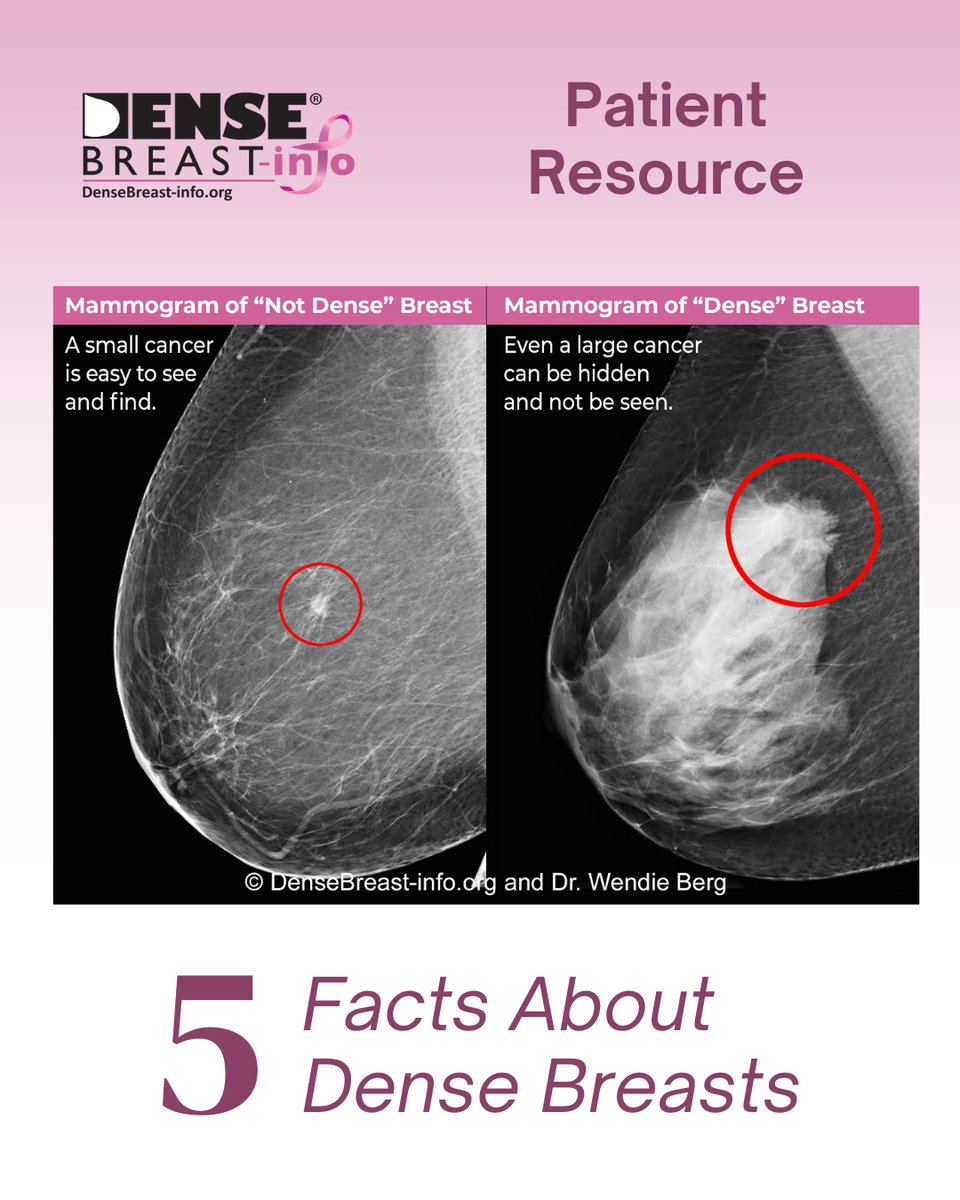

DrWendieBerg explores when a standard mammogram at 40 isn't enough in her article for Mediaplanet USA's #BreastHealth campaign in USA TODAY. Over 20% of women in their 40s need supplemental screening like MRI. ow.ly/RvzB50XHAsV #DenseBreasts #BreastCancerAwareness

Study underscores need for #BreastDensity Notification HIQA Marie Keating Foundation Irish Cancer Society National Cancer Registry Ireland "Women with extremely dense breasts or heterogeneously dense breasts had significantly higher false-negative rates" diagnosticimaging.com/view/mammograp…